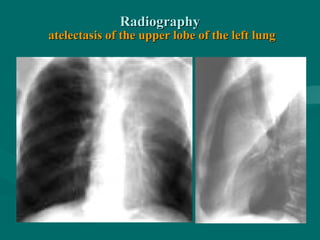

RadiographyRadiography

atelectasis of the upper lobe of the left lungatelectasis of the upper lobe of the left lung

RadiographyRadiography atelectasis of theupper lobe of the left lungatelectasis of the upper lobe of the left lung